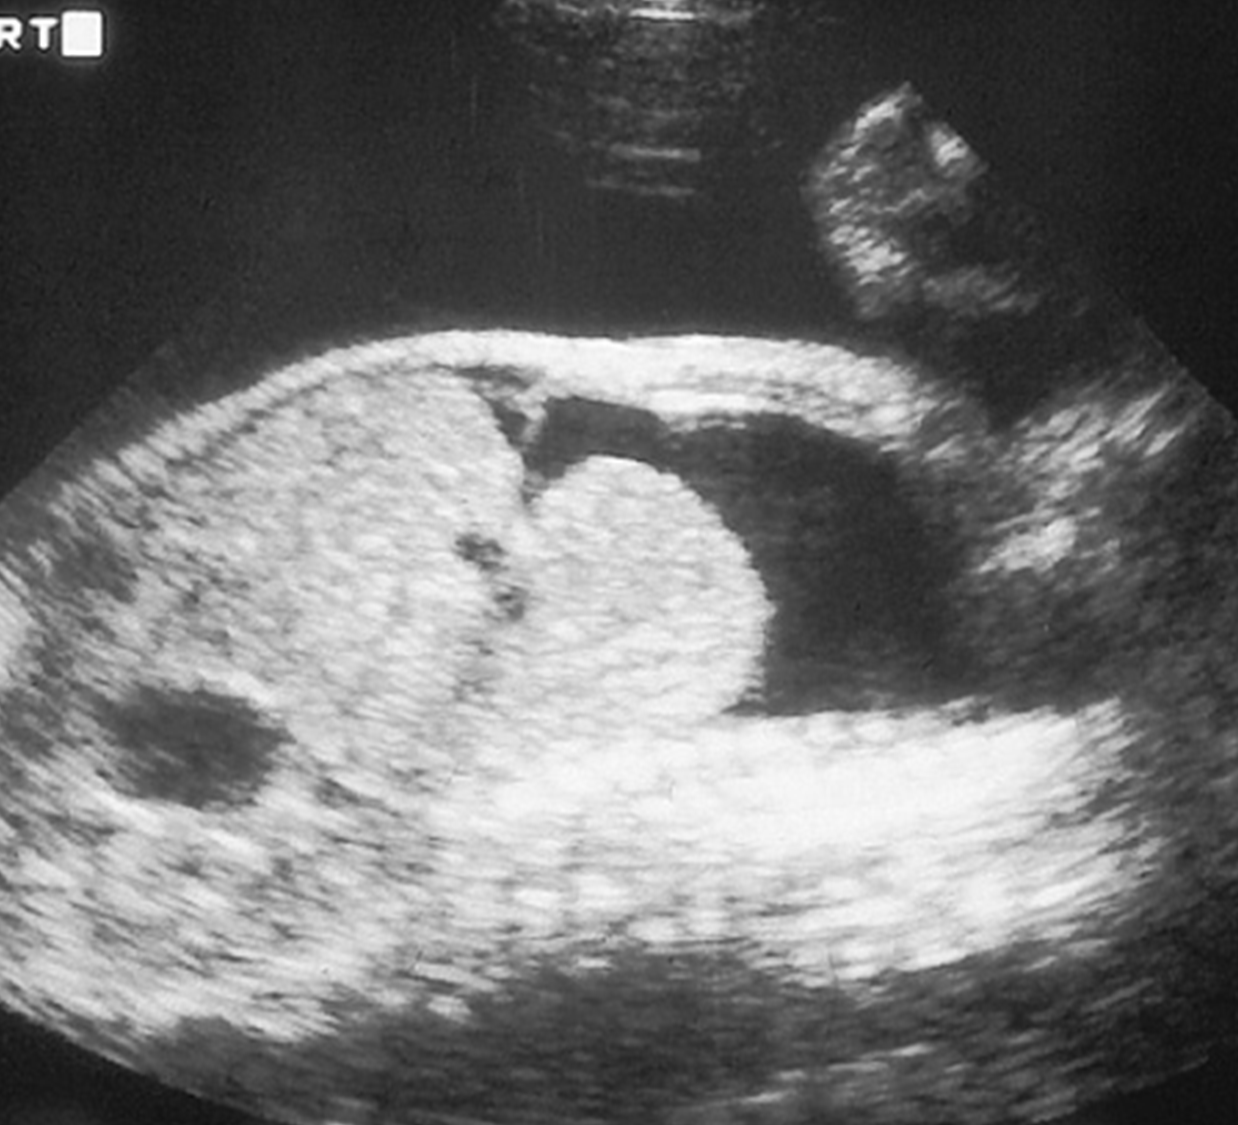

Fetal ascites